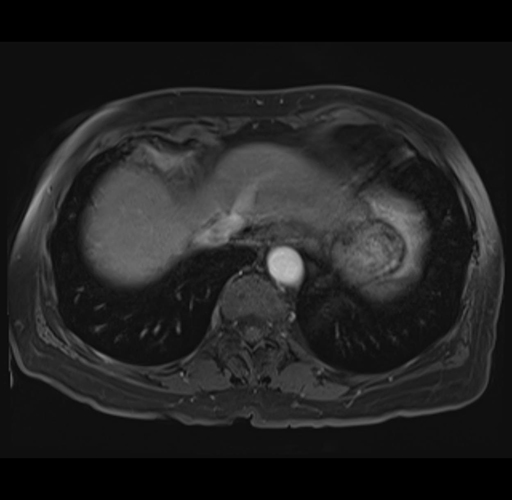

MRI T1